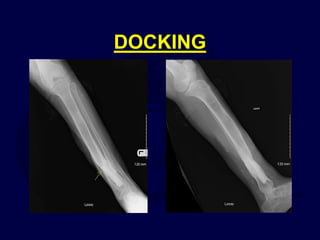

DOCKING

3B tibia with segmental bone loss, 3A

plateau, temporary spanning ex fix

• Converted to circular

frame, limited open

reduction and internal

fixation of tibial plateau

with screws/wires

• Corticotomy

and transport

Consolidation

*note: docking site bone grafted

Union